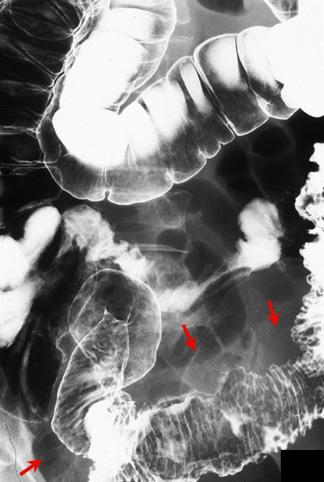

질환(병리주체)의 분류 악성 상피성종양/선암

부위(장기별) 대장/S상

검사방법 X-P

종양의 육안분류 5형(분류불능)/

종양의 최대경(밀리미터) 40이상

종양의 심달도 ss(a1)